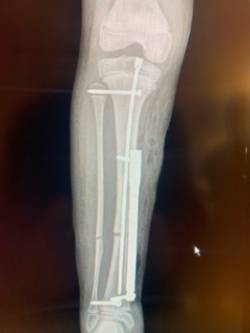

La intervención consistió en la colocación de un dispositivo electromagnético subcutáneo. Tal y como detalla el especialista de Orthopediátrica, en primer lugar, se elige el lugar idóneo para cortar el hueso, punto por el que se alargará, posteriormente se introduce una guía en el interior de la tibia y se corta el hueso y, en último lugar, a través de una pequeña incisión a la altura del tobillo se introduce el dispositivo y se fija al hueso con tornillos. El dispositivo está conectado a un mando que es el que va alargando/distrayendo el hueso en torno a un milímetro al día hasta alcanzar la altura que se ha planificado.

Se trata de un paso más en la cirugía ortopédica infantil, afirma el doctor, que aprendió esta técnica durante su estancia en EEUU, siendo la primera vez que se coloca un dispositivo de este tipo, intradérmico, en lugar de hacerlo intraóseo.

Según el cirujano ortopédico pediátrico integrado en IHP, esta nueva técnica está especialmente indicada para pacientes pediátricos, en los que el tamaño del hueso no permite alojar el clavo en su interior o que aún tienen los cartílagos de crecimiento abiertos. En este sentido, ha explicado que la intervención en tibias para colocar el clavo intramedular no es recomendable hasta los 14 años, ante el riesgo de provocar daños secundarios al atravesar la placa de crecimiento del hueso.

Finalmente, el doctor Javier Downey detalla que el proceso de alargamiento comienza a la semana de la intervención, denominada ‘fase de distracción’, que suele durar aproximadamente dos meses. Una vez conseguida la longitud deseada, se inicia la ‘fase de consolidación’ que dura alrededor de tres meses y que permite que el hueso regenere y se fortalezca. A partir de este momento, el paciente puede hacer vida normal y, aproximadamente al año de acabar la distracción se retira el clavo. La duración del proceso dependerá del progreso de cada paciente, que desde el inicio y hasta la retirada del clavo deberá someterse a tratamiento de fisioterapia.